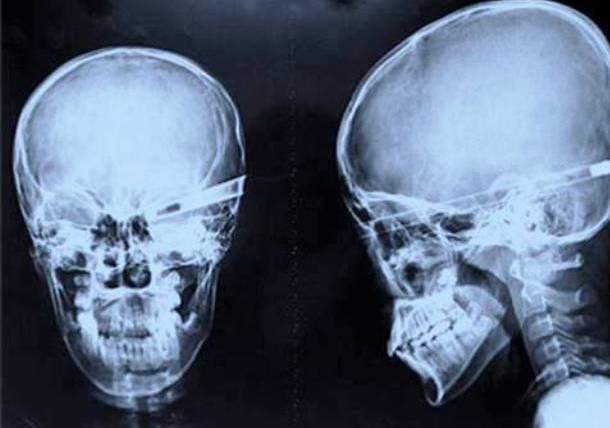

6. Mũi tên 'xuyên táo'

Trẻ con thì hay chơi đánh trận giả, nhưng mà chơi nhập tâm tới mức này thì hơi quá đáng. Một cậu bé Trung Quốc không hiểu làm gì mà đã nhập viện trong tình trạng bị một mũi tên xuyên qua đầu, theo đường hốc mắt xuyên cả ra phía sau hộp sọ. Và kỳ lạ làm sao mà cậu bé này vẫn vượt qua tất cả để tiếp tục sống khỏe mạnh với thị lực giảm xuống ở mức 'Thế Chột'.